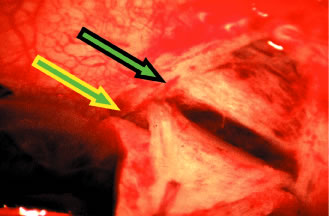

chamber reformation is necessary. The anterior chamber is entered by incising through the sclera in a radial

fashion, along the right-hand line of radially placed cautery. Multiple

light scratches are placed, and the blade is kept vertical so that

entry will be as close as possible to the anterior extent of the scleral

flap. A sharp blade such as a diamond knife or superblade can be

employed, but unless used with a guard, these blades are likely to penetrate

into the iris. These sharper, more pointed blades make it possible

to enter more anteriorly, which is a real advantage. But they must

be used cautiously to avoid damage to the iris and lens, with subsequent

development of cataract. The incision is made long enough so that its posterior edge is just posterior

to the junction between the white sclera and the clear cornea. If

the posterior extent of the incision is not long enough at the time

of entry, the incision is lengthened. Vannas scissors are placed into

the anterior chamber, with the surgeon making certain that the tip neither

penetrates into the iris nor splits the sclera. This entry is assisted

by lifting the area to be excised with a fine forceps, such as

a Pierce-Hoskins forceps, and depressing the bed of the sclera with the

edge of the Vannas scissors. The scissors must not be directed in an

angled fashion so that they extend through the iris into the lens and

underlying zonules. After the radial groove has been made, the block must be excised. There

are advantages to cutting the anterior aspect of the block first, and

advantages to cutting the posterior edge of the block first. To some

extent, the method that is used depends on each eye and what occurs at

the time of the surgery. Once the Vannas scissors is placed so that one

blade is definitely in the anterior chamber, it can be moved anteriorly

as far as possible so that it pushes firmly against the base of the

scleral flap, where it is attached to the cornea. In the right eye, it

usually is easier to use the right hand to hold the Vannas scissors. The

left hand is used to fix the sclera at the posterior edge of the

bed. The left hand pulls the globe superiorly in the direction of the

brow, and the right hand pushes the Vannas scissors inferiorly toward

the nose. The goal is to ensure that the section is placed as far anteriorly

as possible, so that no ledge of cornea will be left. The blade

of the Vannas scissors should be held exactly perpendicular to the

cornea so that the cut is not shelved. The outer blade should be directly

over the inner blade, as shown in Figure 15G. Once the anterior aspect of the block has been cut, the fixation on the